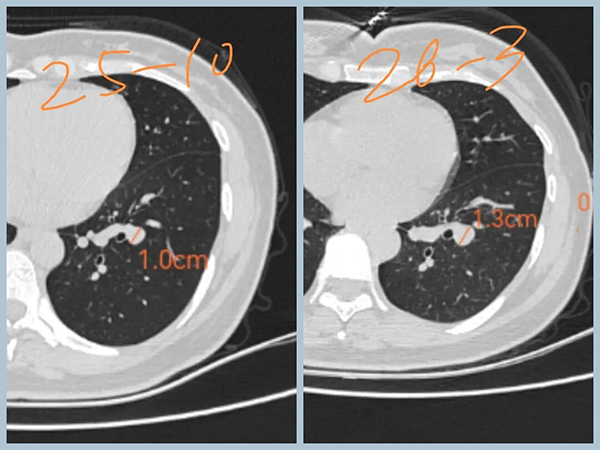

女性,30+,发现双肺结节5个月

分别是右肺上叶纯磨玻璃结节,大小约8mm

左肺下叶实性结节,大小约1cm

5个月后复查,右肺磨玻璃结节无变化,左肺实性结节增大

下一步怎么办:

1、磨玻璃结节无增大,原位癌可能,可继续观察

2、左下叶结节增大,有可能是低度恶性肿瘤,如类癌。也可能是良性病变,如错构瘤、硬化性肺泡细胞瘤。半年后再复查,继续增大,建议手术。